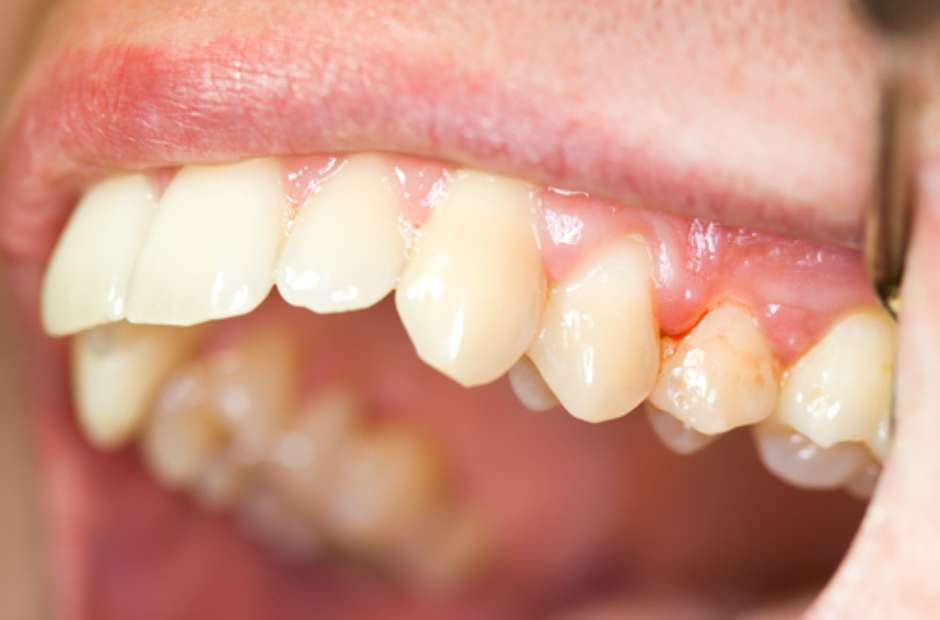

A base do tratamento para qualquer doença periodontal é a remoção mecânica das causas: placa bacteriana e cálculo (tártaro). A terapia não cirúrgica, que inclui a Raspagem e Alisamento Radicular (RAR), é o primeiro e mais importante passo. Ela visa criar um ambiente bucal limpo para que a gengiva possa cicatrizar e se reaproximar do dente.

Vamos combinar: a periodontite agressiva é uma condição crônica. Isso significa que o controle é para a vida toda. Após o tratamento inicial, as consultas de manutenção periodontal são essenciais. Elas envolvem limpezas regulares e avaliação para detectar precocemente qualquer sinal de retorno da doença. Sua higiene bucal em casa, feita de forma correta e consistente, é a sua principal arma para manter a saúde gengival e óssea.

- Foco na Prevenção Contínua: Mesmo após o tratamento, a higiene bucal diária rigorosa é sua maior aliada. Use fio dental todos os dias e escove os dentes corretamente após as refeições.

- Visitas Regulares ao Dentista: Consultas de acompanhamento são essenciais para monitorar a saúde das suas gengivas e intervir precocemente caso haja qualquer sinal de retorno da doença.